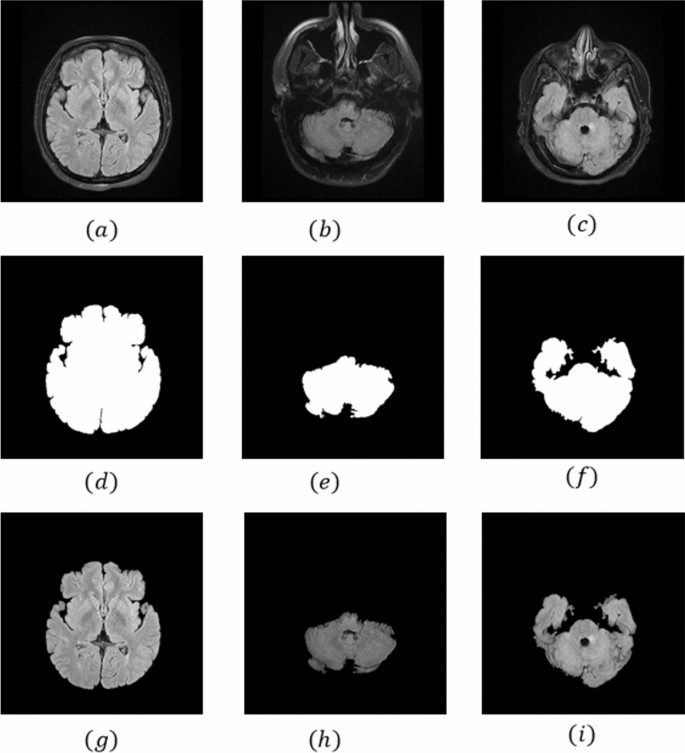

Pre-processing

To improve the data, dataset pre-processing was done. It was employed to improve the data's compatibility with subsequent steps. Removal of the cranial bone segment of the skull, resizing, and normalization were the pre-processing steps carried out in this study. In the following sections, a thorough explanation of various pre-processing steps is provided.

In the preprocessing stage, to eliminate the surrounding cranial bone segment of the skull from our images, could after applying the 3 × 3 median filter, use a combination of the Gabor filter and morphological operation.

After applying the Gabor filter by these parameters and morphological operators to the image, thus separating the brain parenchyma tissue from the rest of the image, and our images were ready for training the target network. Figure 1 shows all these steps for three images in general.

Resizing

Changing all of the images in the dataset to a specific size is referred to as resizing. We needed to resize the dataset because the neural network only receives images that are the same size. The image is 256 * 256 * 1 in size after the resizing step.

Normalization

To convert all of the image's pixel values between 0 and 1, a process known as normalization was used. Each pixel value is divided by 255 to accomplish this.